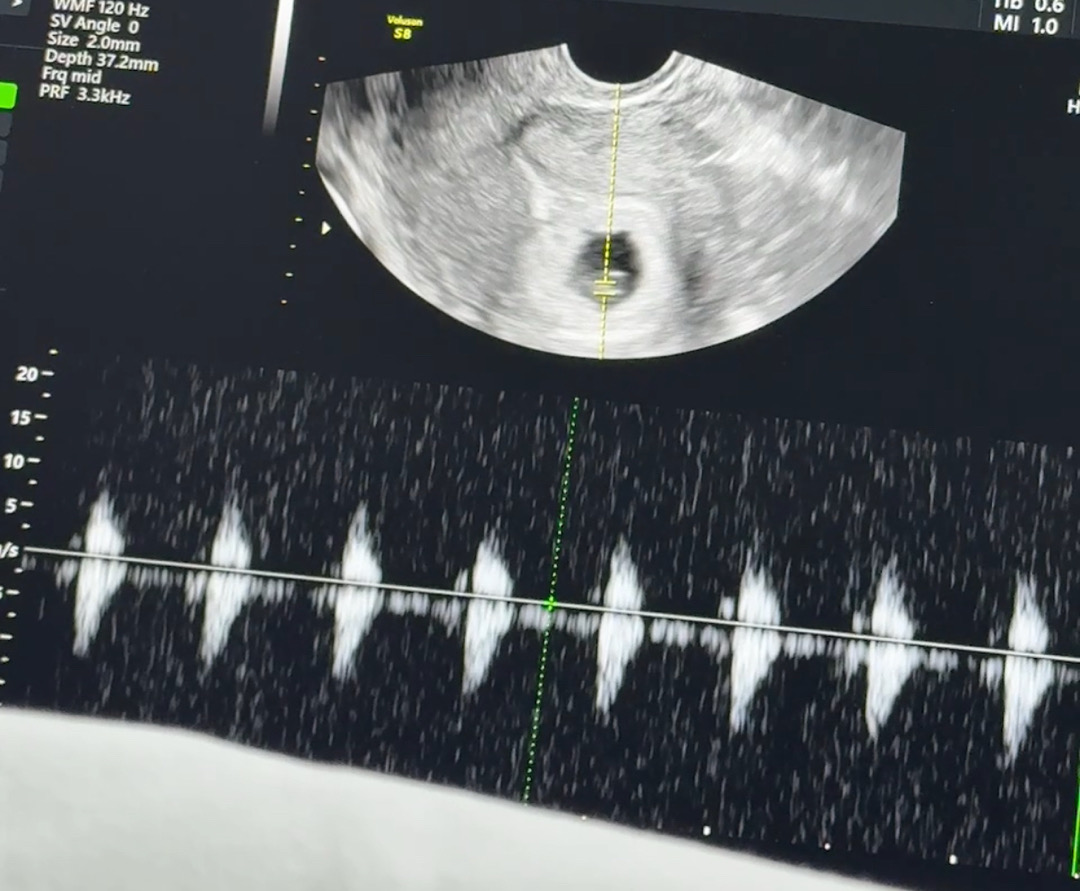

심소듣고왔어요🥹

둘째여도 감동은 똑같네요!🥹 막생 7월 2일이고 저번주 토요일에 병원 갓을땐 난황만 보고왔는데 오늘 다른 병원은 아니고 제가 사는 동네가 분만취약지역? 이래서 보건소에서 격주로 산모들 초음파봐주거든요! 오늘 차트만들겸 갓는데 심소들을거란 기대는 안하고 갓는데 심소들려주시더라구요ㅠㅠ 그동안 맘조린거 생각나서 울컥했네요! 우리 같이 끝까지 힘내봐요!